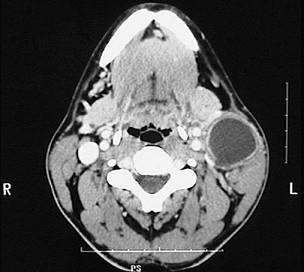

图示是鳃裂囊肿患者的CT 检查结果,关于此病的描述错误的是  (    )

A可形成瘘

B可继发感染

C大小不定,生长缓慢

D无自觉症状

E触之有搏动感